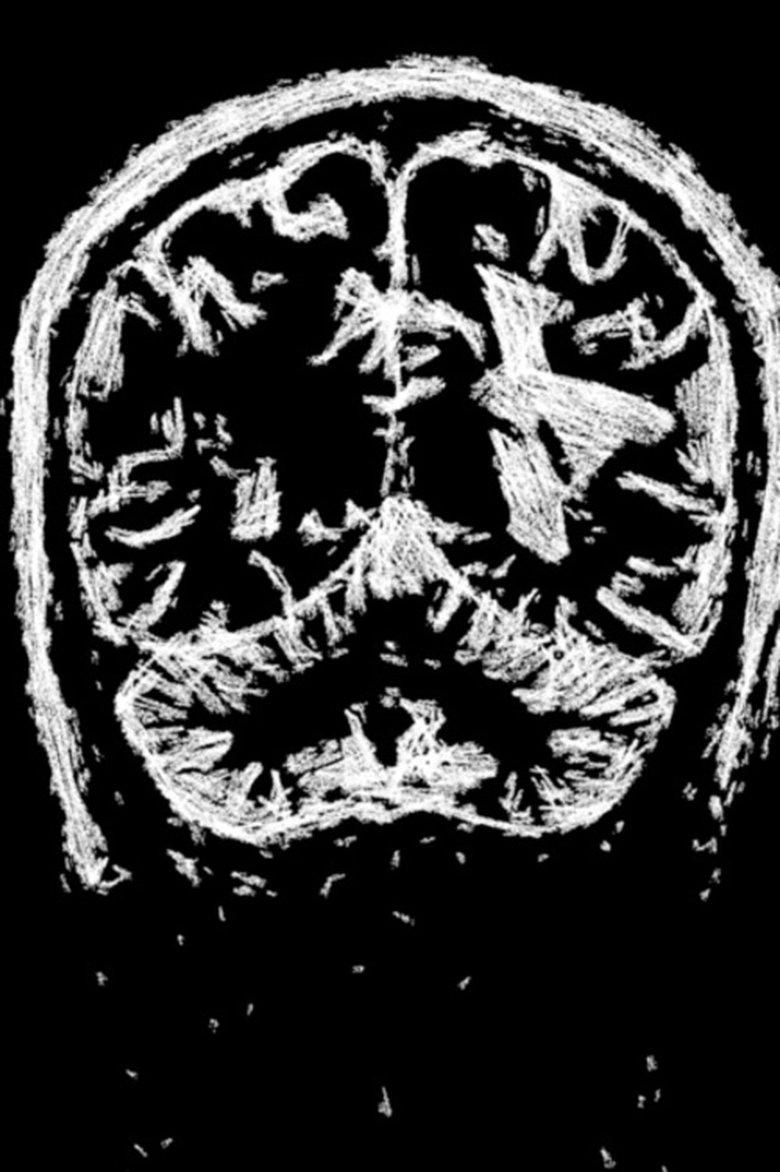

Plot: Inspired by the poem of the same name by the poet Atso Shopov, the director of the film confronts his father's terminal illness and the transience of life. The film is mainly composed of animatied MRI scans of the now late parent